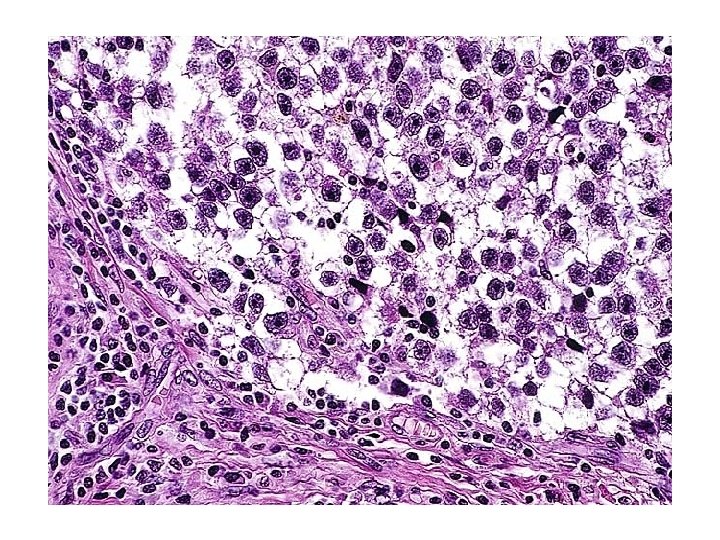

Seminoma

Seminoma Syncytiotrophoblast